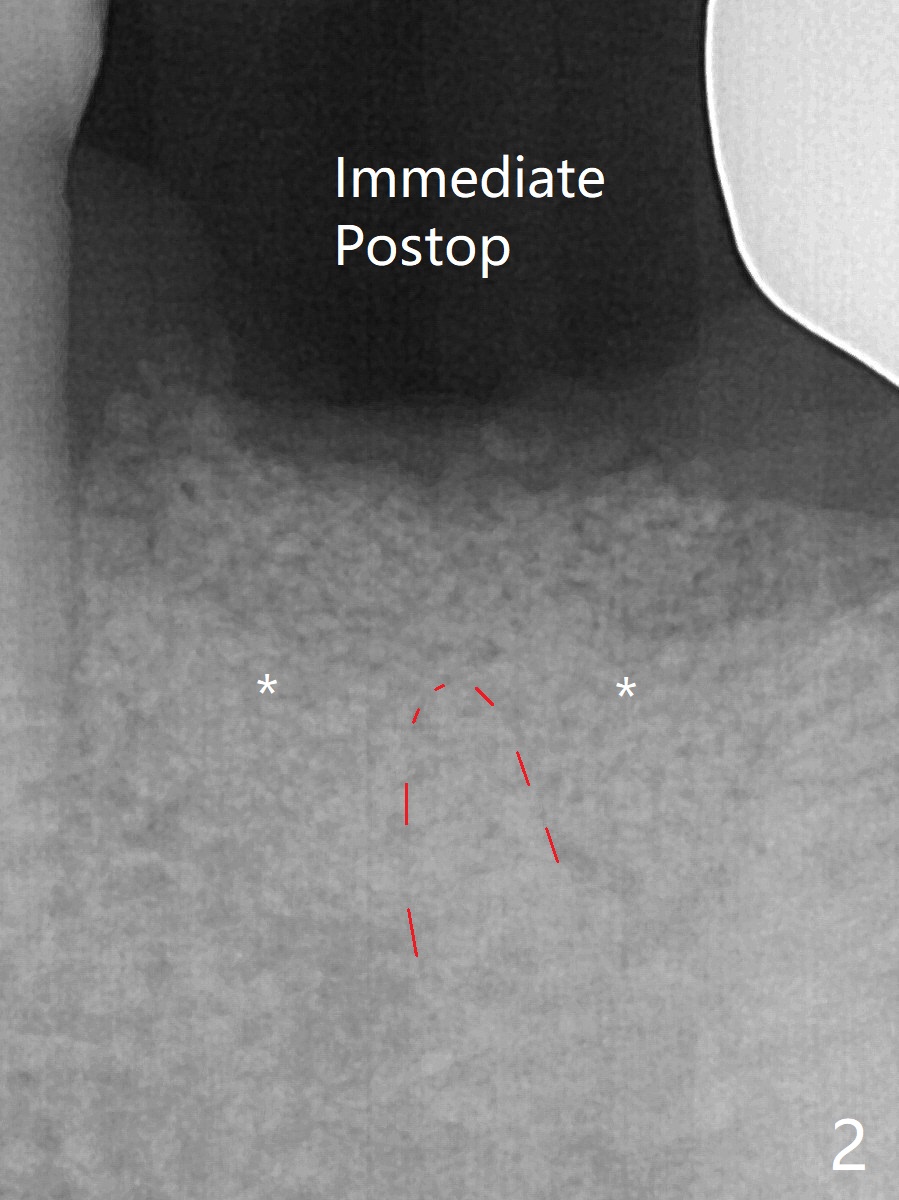

A 58-year-old man requests extraction of the tooth #19 with supraocclusion (Fig.1). After extraction, the septal gingiva has to be sectioned to remove underlying granulation tissue thoroughly. The buccal plate is missing. Ossogen (allograft, Fig.2 *) is placed around the septum (red dashed line). The socket opening is covered by BioXclude and approximated with 4-0 PGA suture, followed by periodontal dressing. With the septum's support, bone graft is expected to heal without too much ridge collapse. The mesial and distal sockets behave as 2 small premolar ones, getting ample blood supply. The socket heals in 20 days (Fig.3). The sockets heal with preservation of the septum (Fig.4: S), while there is formation of the cortical plate on the top of the ridge 10 months postop (Fig.5: ^). It is safe to place a 5x10 mm implant with guide (Fig.6), whereas it may be necessary to place bone graft lingual to the implant at #18 associated with free hand surgery (Fig.7: >). Return to Lower Molar Immediate Implant, No Deviation 18 种植 位点保存 Xin Wei, DDS, PhD, MS 1st edition 01/22/2020, last revision 07/03/2021